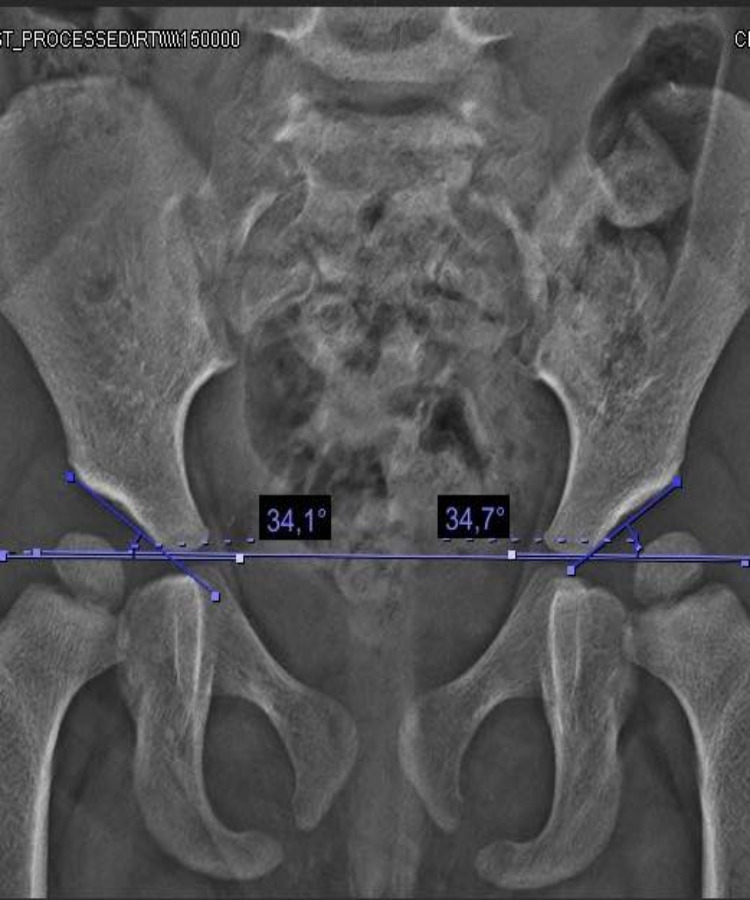

Rodillas en Valgo

conocer másLas deformidades de pie y rodilla incluyen genu varo, genu valgo, pie plano y pie cavo, con causas congénitas o postraumáticas.